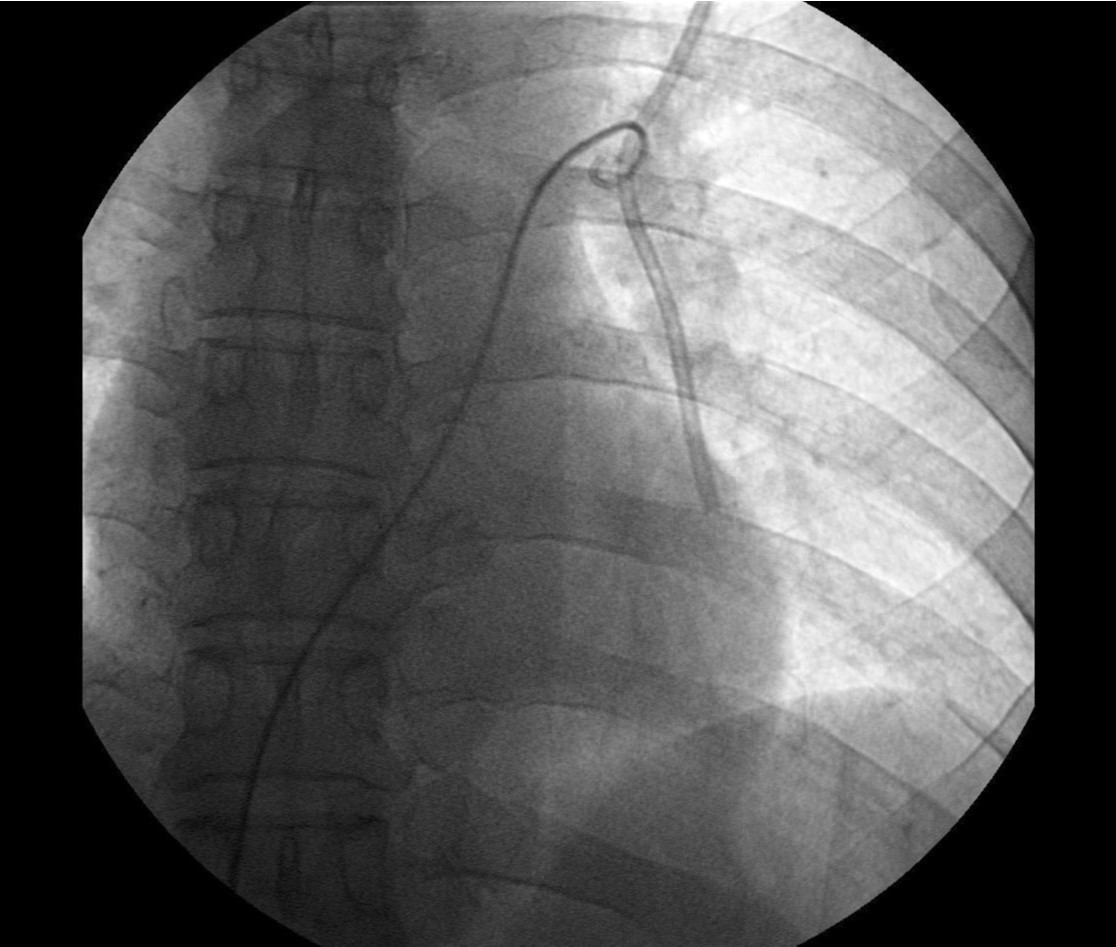

Fig. 4. B

(B) Twisting of pigtail catheter in main trunk of left pulmonary artery.